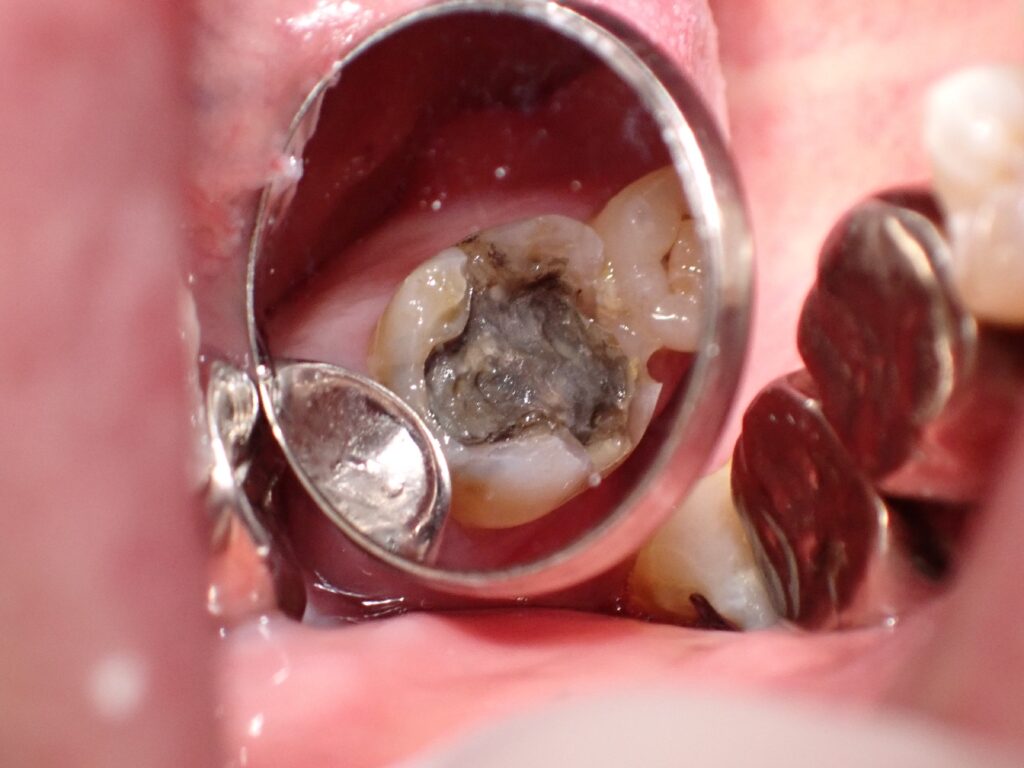

実は、銀歯を外してみると、その下が真っ黒なむし歯になっていた…というケースが非常に多いのです。 今回は、安城市のかみやデンタルクリニックが、写真とともに「銀歯の下のリスク」について解説します。

「痛くないのに、本当にむし歯なの?」 そう思われるのも無理はありません。しかし、百聞は一見にしかずです。まずはこちらのお写真をご覧ください。 (※むし歯の状態を示す写真が含まれます)

一見問題なさそうに見える銀歯でも、長い年月が経つと接着剤(セメント)が溶け出し、歯と金属の間に「ミクロの隙間」が生まれます。そこからむし歯菌が侵入し、気づかないうちに内部で進行してしまうのです。 これを「二次むし歯(二次カリエス)」と呼びます。